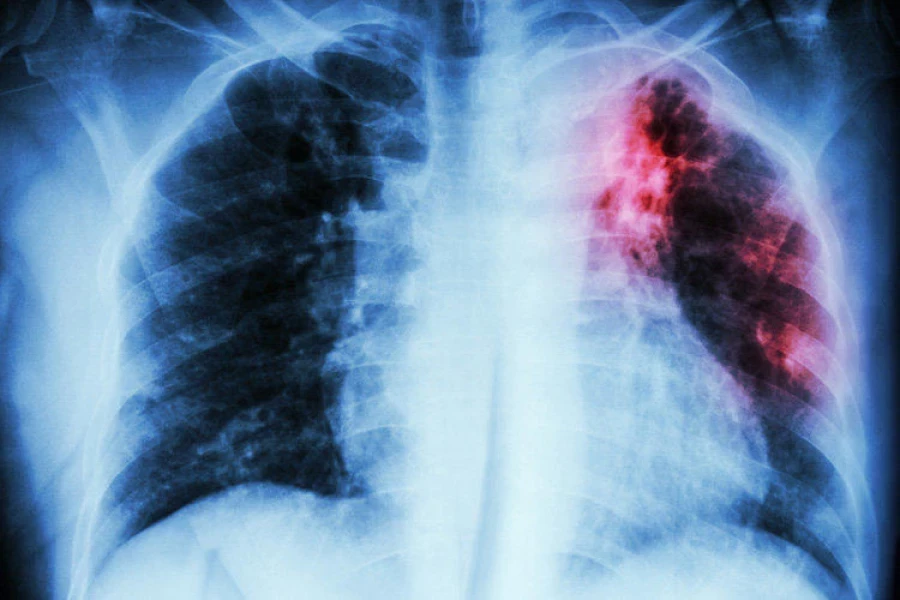

«Бишкекте туберкулезди диагностикалуу иштер активдүү жүргүзүлүүдө. Ар бир мектеп тубдиагностика уюштурат. Бирок аймактарда кырдаал башкача: туберкуллиндин жетишсиздиги, диагностика иштерине муктаж адамдар үчүн чектелген жеткиликтүүлүк жана флюорография аппараттарынын жетишсиздиги байкалууда», - деп түшүндүрдү ал.

«Жогорку ички миграциянын кесепетинен биз жыл сайын туберкулез боюнча диагностика жүргүзөбүз. Мартта мугалимдер жана өспүрүмдөр үчүн маалыматтык-билим берүү иш-чараларын өткөрүүнү пландап жатабыз. Флюорография 15 жаштан жогорку адамдар тарабынан өтүлөт, ал эми мугалимдер менен медициналык кызматкерлер муну аткарышы зарыл, анткени болбосо жумушка алынбайт. Бирок, көптөгөн адамдар өлкө боюнча көчүп кете турганын эске алса, алдын алуу иштерин күчөтүү зарыл, өзгөчө кызмат көрсөтүү тармагындагы кызматкерлер үчүн. Ата-эне болуп саналган адамдар үчүн маалыматтык иштер, ошол эле кезде массалык маалымат каражаттары аркылуу жүргүзүлүшү маанилүү. Эгер алар туберкулездин коркунучун аңдаса, өз балдарын жакшыр карда кире турган болушат», - деп эсептейт Бактыгуль Жумагулова.

Чынтемир Осмонов атындагы мектепте, Иссык-Куль областынын Ак-Суй районунун Курбу айылында, жыл башынан бери 15 окуучуда туберкулез аныкталганын белгилеп кетүү керек. Бул тууралуу депутат Камила Талиева Жогорку Кеңештин жыйынында билдирди.